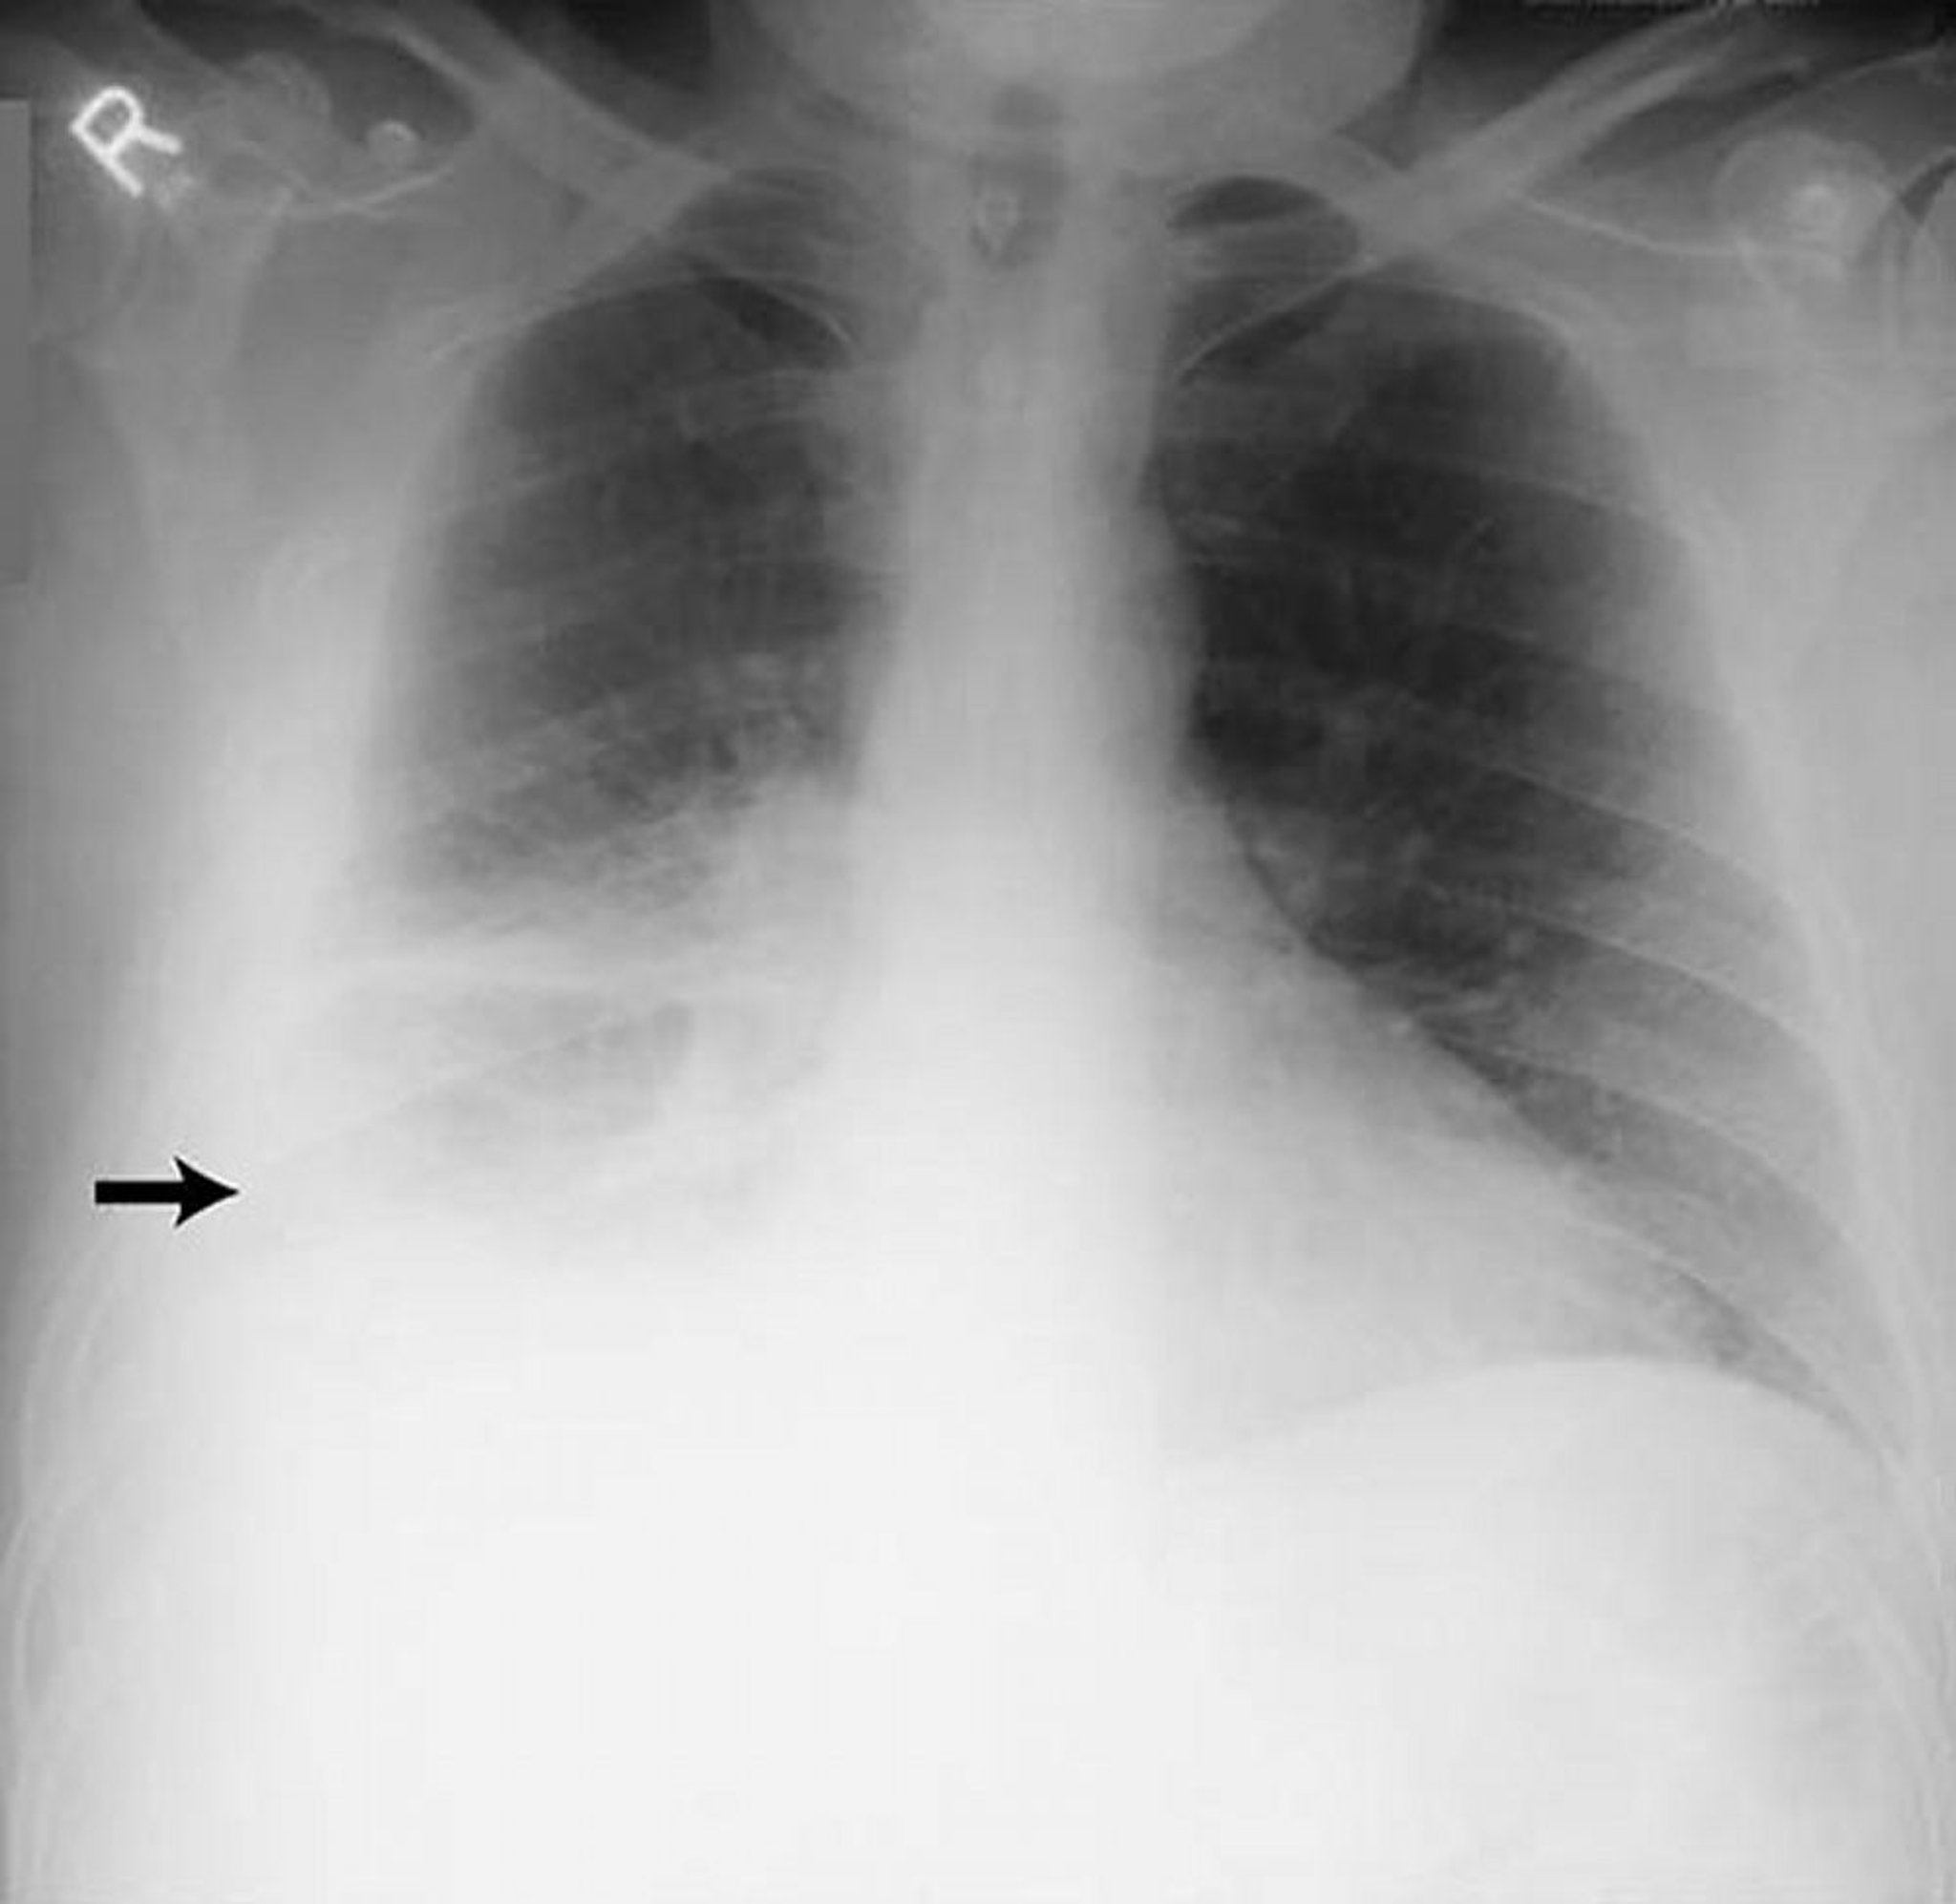

Derrame pleural extenso

Esta imagen muestra un derrame pleural derecho extenso (flecha) en un paciente con pleuritis reumatoide.

By permission of the publisher. From Huggins J, Sahn S. In Bone's Atlas of Pulmonary and Critical Care Medicine. Edited by J Crapo. Philadelphia, Current Medicine, 2005.